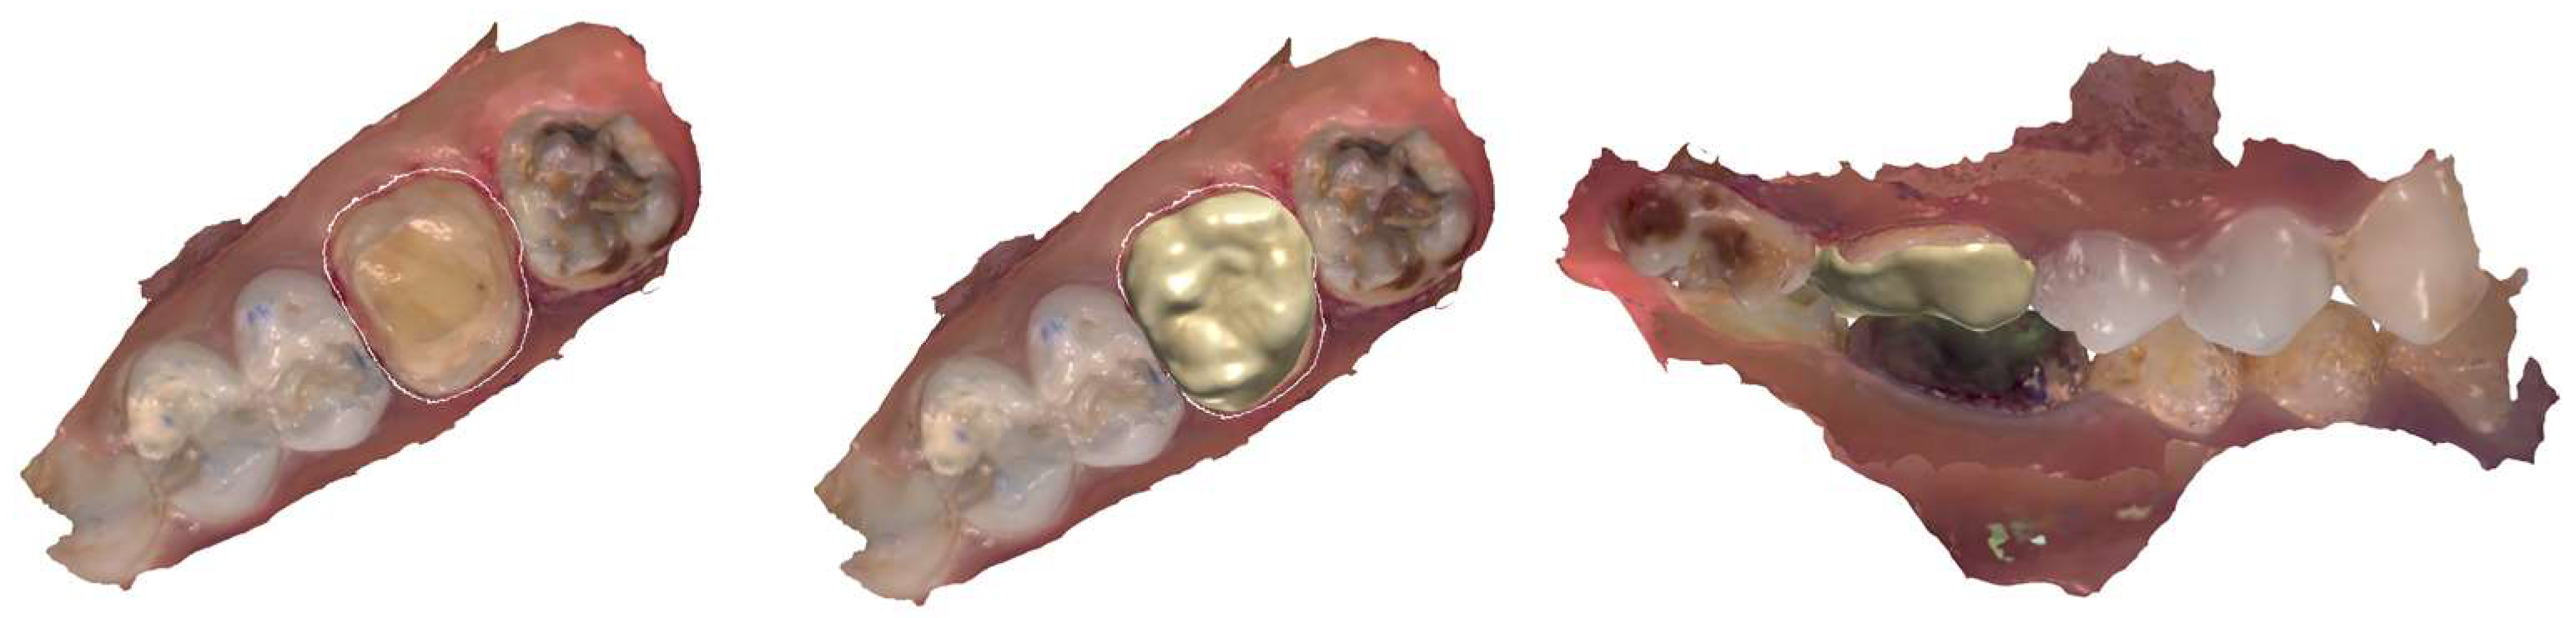

2.8. Management of the Maxillary Molars (Third and Fourth Sessions)

2.8.1. Third Session

2.8.2. Fourth Session